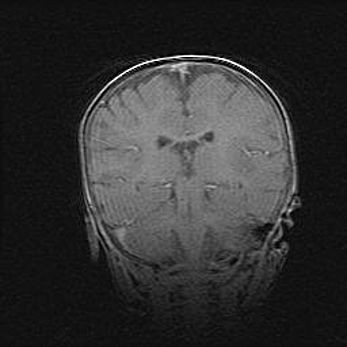

Церебральная ишемия II.

Возраст: 7 дней

Вес: 3350 г

Пол: женский

Окружность головы: 35 см

Срок гестации: 39 недель

Ишемия головного мозга – это состояние, которое развивается в ответ на кислородное голодание вследствие недостаточного мозгового кровообращения. У новорожденных она является следствием дефицита кислорода, что ведет к метаболическим расстройствам различной степени тяжести в тканях головного мозга, в том числе к развитию коагуляционных некрозов и гибели нейронов.